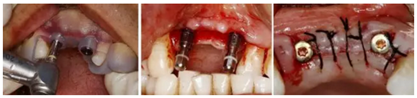

(2)數(shù)字化3D種植外科導(dǎo)板的設(shè)計(jì)制作

(3)數(shù)字化3D種植外科導(dǎo)板引導(dǎo)下Straumann 3.3x12 NC 種植體行延期種植

美學(xué)區(qū)連續(xù)多牙缺失使術(shù)者臨床操作中缺乏直觀的植入?yún)⒖紭?biāo)志,會(huì)產(chǎn)生嚴(yán)重的美學(xué)風(fēng)險(xiǎn)。以修復(fù)為導(dǎo)向設(shè)計(jì)配合3D打印技術(shù)的數(shù)字化種植外科導(dǎo)板,保證了種植體三維位置的精確,為種植體長(zhǎng)期穩(wěn)定性提供了保障。